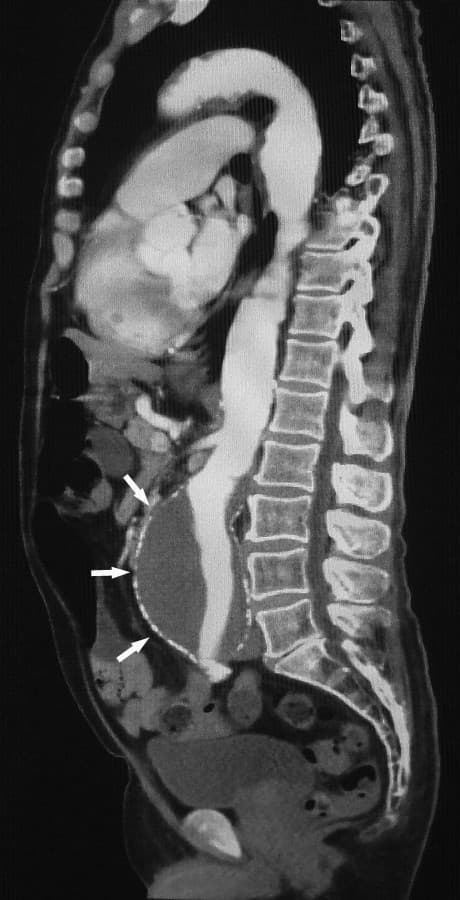

Computed tomography angiography